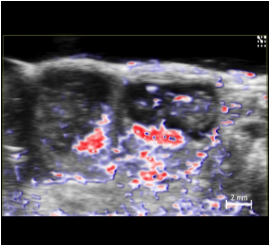

超音波による高い分解能・深度に加え、光イメージングの感度・特異性を同時に得ることが可能

フォトアコースティックによる機能的情報は、超音波のB-Mode画像上に統合・オーバーレイ表示できる為、解剖学的位置情報と共に解釈する事が可能です。

- 酸素飽和度・総ヘモグロビン量の算出(解剖学的B モード画像との統合表示、0.5Hz)

- ナノ粒子を用いたコントラストイメージング・様々な受容体/リガンド/抗体/タンパク質/分子を標的としたターゲットイメージング